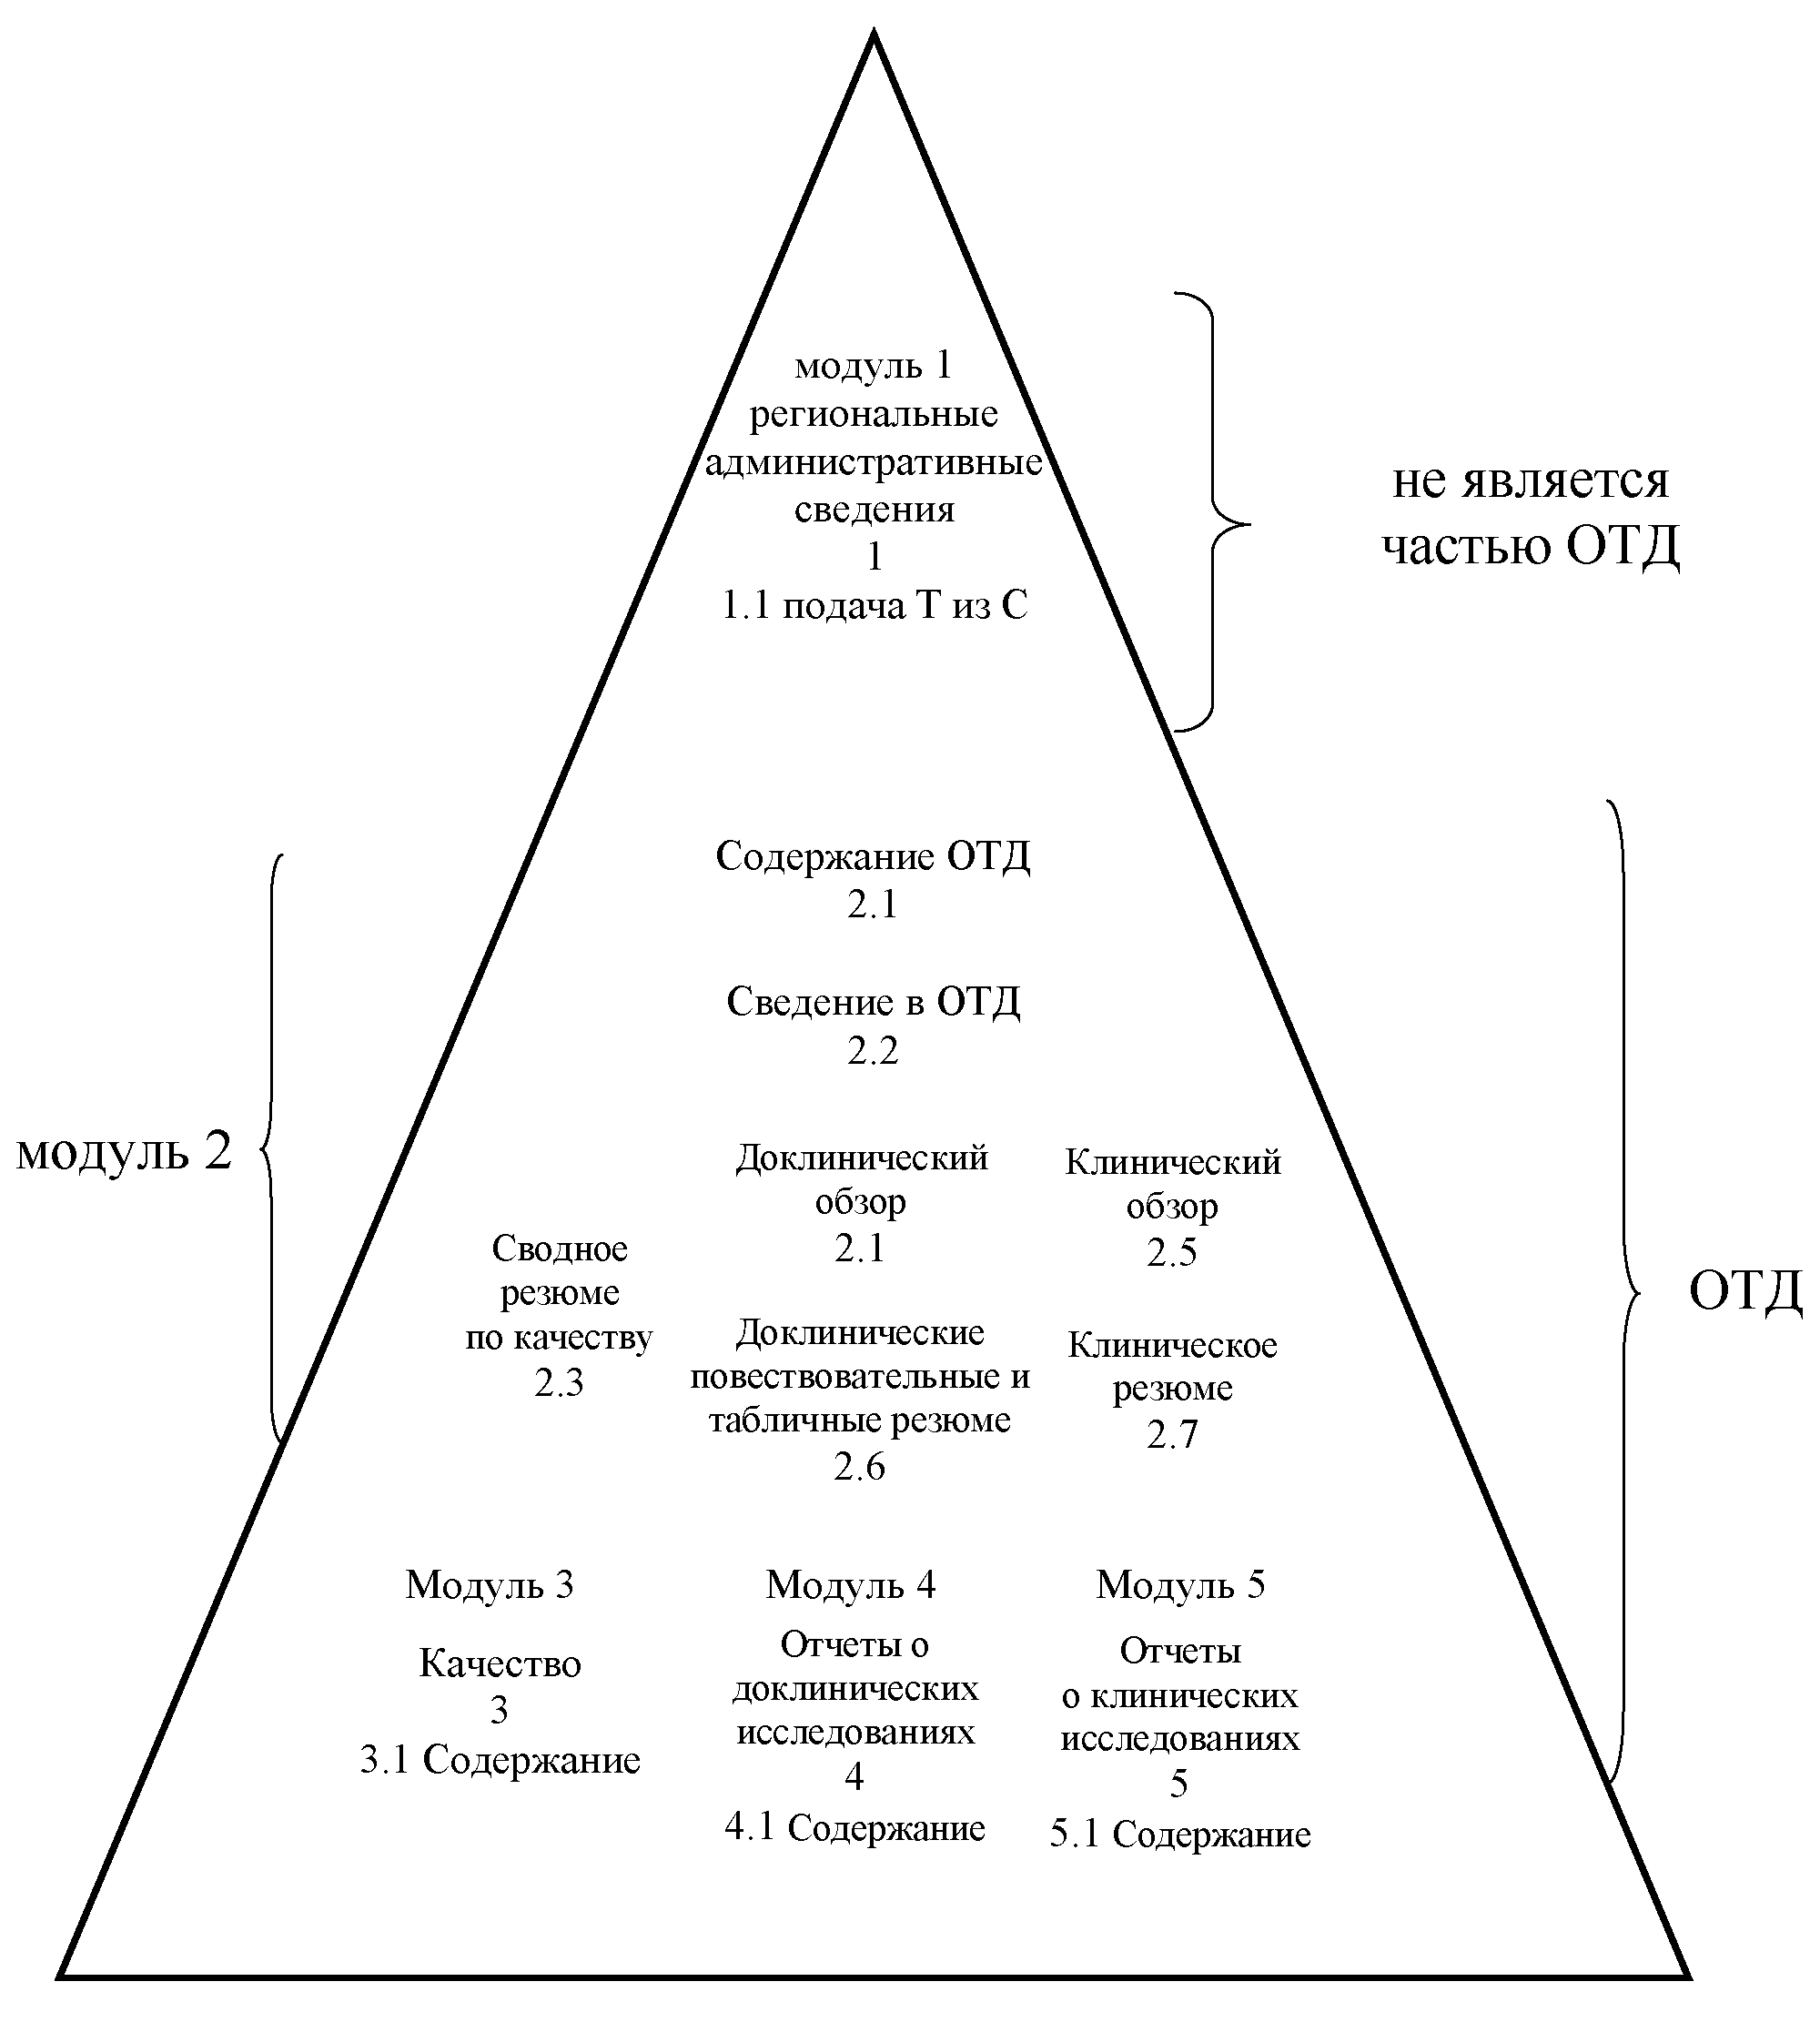

25. Требования к документам и данным регистрационного досье в формате общего технического документа, представляемого на регистрацию лекарственного препарата, установлены приложениями № 1 - 5 к настоящим Правилам.

36. При регистрации лекарственного препарата отчеты о проведенных клинических исследованиях, включенные в состав модуля 5 его регистрационного досье, рассматриваются в процессе экспертизы при соблюдении одного из следующих условий:

регистрационное досье в соответствии с приложениями № 1 - 5 к настоящим Правилам на электронном носителе (дополнительно модуль 1 регистрационного досье представляется на бумажном носителе (за исключением плана управления рисками, основного досье (мастер-файла) производственной площадки (производственных площадок) и мастер-файла по фармаконадзору));